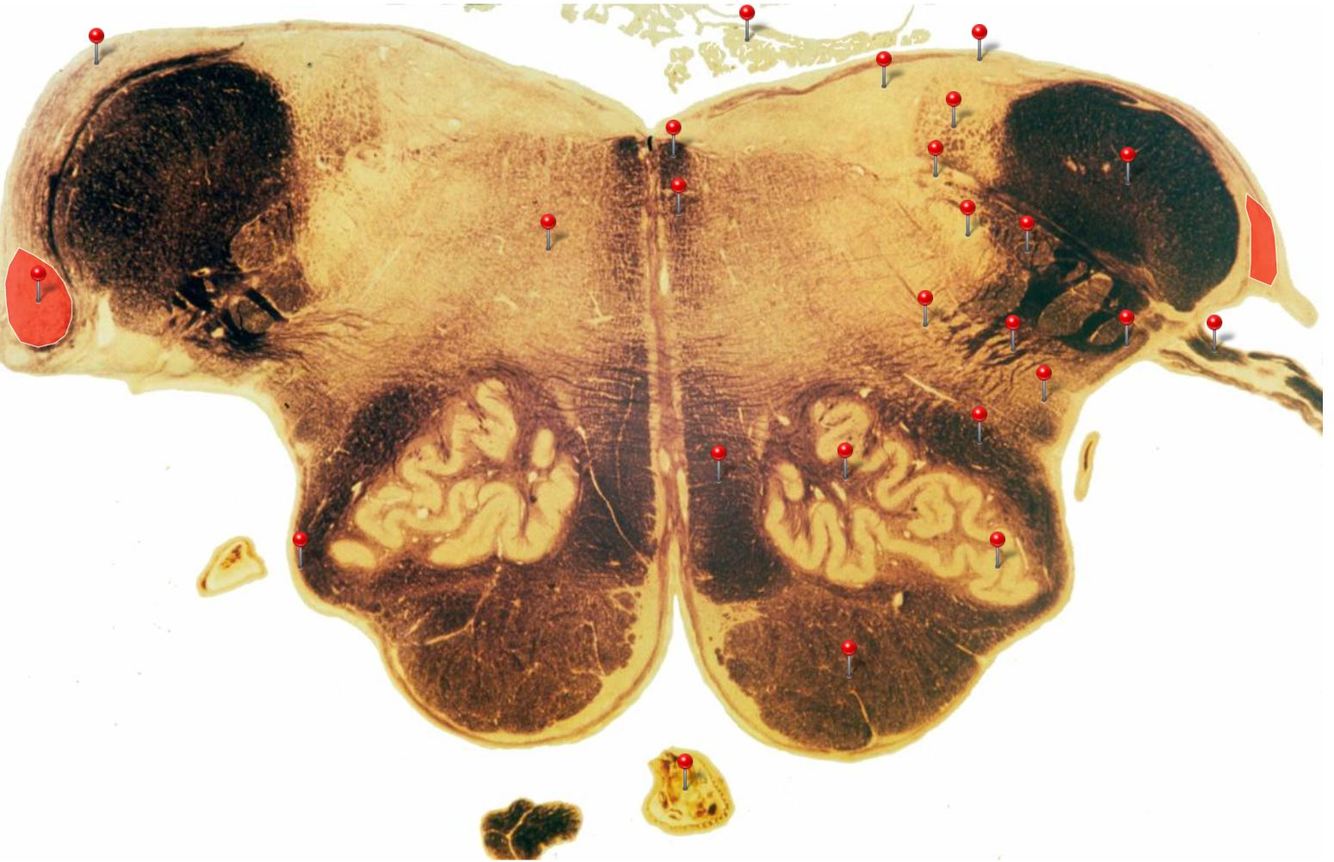

11

Q

A

Corticospinal Tract

Rostral Medulla

Controls precision and speed of skilled movements involving the distal muscles of the contralateral limbs, particularly those of the hands and fingers

12

Nucleus Ambiguus

Neurons supply the muscles of the pharynx, larynx, upper oesophagus and heart

13

Basilar Artery

Provides blood supply to much of the cerebellum, pons, midbrain and posterior thalamus as well as part of the temporal (inferior surface) and occipital (medial and inferior surfaces) lobes

14

Olives

Elevations formed by the inferior olivary nuclei which integrate information from a variety of sources before relaying it to the cerebellum

15

Rubrospinal Tract

Assists in the control of movements of the hands and fingers

16

Medial Vestibular Nucleus

Process inputs from vestibular receptors of the inner ear and are involved in the regulation of posture and the coordination of head and eye movements

17

Spinal Trigeminal Tract

Transmits somatosensory (crude touch, pain and temperature) inputs from the Trigeminal nerve (CN V) through the midpons and medulla to the spinal trigeminal nucleus.

18

Ventral Cochlear Nuclei

One of the relay nuclei for the auditory fibres of the vestibulocochlear nerve (CN VIII) and functions to modify inputs to the higher auditory structures

19

Medial Longitudinal Fasciculus

Pathway through which eye movements are coordinated with changes in head position

20

Dorsal Cochlear Nuclei

One of the relay nuclei for auditory fibres of the vestibulocochlear nerve (CN VIII) and functions to modify inputs to the higher auditory structures